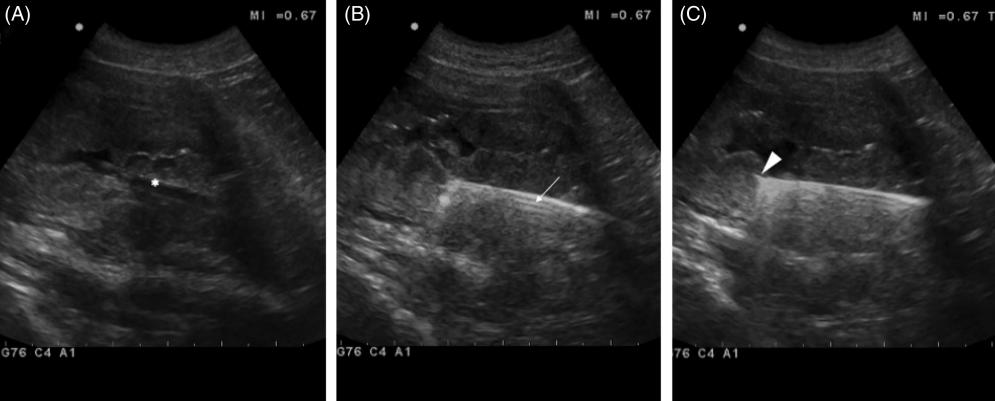

초음파와 내시경 포셉을 이용한 방광 조직생검 방법

내시경 검사를 할때 위장관 조직을 생검하던 바이옵시 포셉을 이용하여 방광내 TCC와 같은 종양을 조직 생검하는 방법에 대한 논문

당연히 샘플링 위치는 초음파 유도하에 한다.

물로 샘플링된 조직의 총량은 수술적인 방법보다는 적지만 그래도 FNA를 했을때나 suction byopsy를 했을때보다 많고

복강내 seeding 가능성도 낮아 시도해볼만하다.